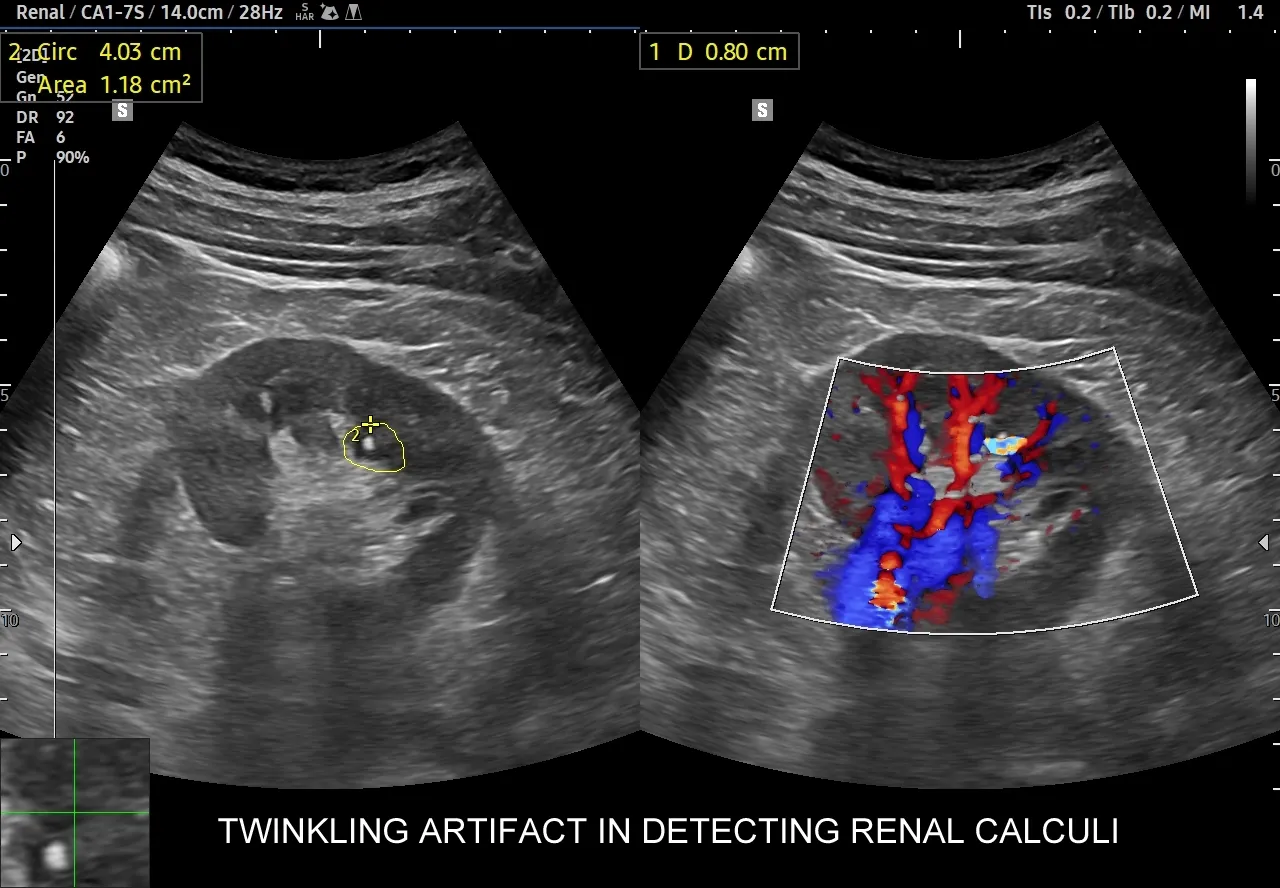

USG układu moczowego jest zazwyczaj pierwszym badaniem obrazowym, które zleca się przy podejrzeniu kamicy nerkowej, szczególnie w przypadku kolki nerkowej. To badanie jest szybkie, nieinwazyjne i całkowicie bezpieczne, ponieważ nie wykorzystuje promieniowania jonizującego. Dzięki temu jest preferowaną metodą diagnostyczną u dzieci i kobiet w ciąży. USG pozwala na uwidocznienie kamieni o wielkości powyżej 3-4 mm, określenie ich lokalizacji w nerkach i górnych drogach moczowych, a co najważniejsze sprawdzenie, czy nie doszło do zastoju moczu, czyli wodonercza. Wodonercze jest sygnałem, że kamień blokuje odpływ moczu, co wymaga szybkiej interwencji.

Kiedy potrzebujemy absolutnej precyzji, wkracza niskodawkowa tomografia komputerowa bez kontrastu (CT KUB). Jest ona obecnie uznawana za "złoty standard" w diagnostyce kamicy nerkowej. Jej czułość wynosi aż 95-100%, co oznacza, że jest w stanie wykryć niemal wszystkie typy kamieni, niezależnie od ich składu chemicznego nawet te, które są niewidoczne w RTG. TK precyzyjnie określa wielkość i położenie kamienia, co jest kluczowe przy planowaniu leczenia, zwłaszcza zabiegowego. Zleca się ją, gdy wynik USG jest niejednoznaczny, gdy kamień jest mały lub trudno dostępny, a także przed każdą interwencją urologiczną, aby mieć pełen obraz sytuacji.